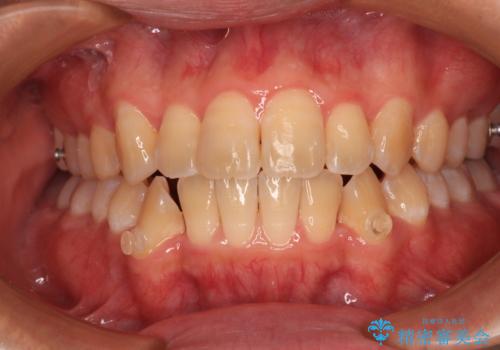

オープンバイトをインビザラインで矯正治療

- 前歯の開咬を気にして来院された患者様です。

開咬の治療は、前歯を閉じるように動かすとともに、上下臼歯を圧下(骨内にめり込ませる)させることで進めて行きます。

インビザラインは臼歯の圧下を効果的に行えるため、インビザラインを用いて矯正治療を行うこととしました。